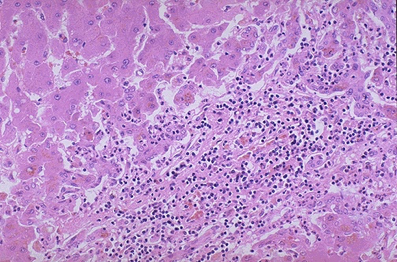

病理变化:肉眼观,肝体积显著缩小,尤以左叶为甚,重量减至600~800g,质地柔软,表面被膜皱缩。切面呈黄*色或红褐色,有的区域呈红黄相间的斑纹状,故又称急性黄*色肝萎缩或急性红色肝萎缩。镜下见肝细胞呈一次性大块坏死(坏死面积≥肝实质的2/3)或亚大块坏死。肝索解离,肝细胞溶解,仅小叶周边部残留少数变性的肝细胞。肝窦明显扩张充血并出血,库普弗细胞增生肥大,并吞噬细胞碎屑及色素。小叶内及门管区有淋巴细胞和巨噬细胞为主的炎细胞浸润。残留的肝细胞再生现象不明显。